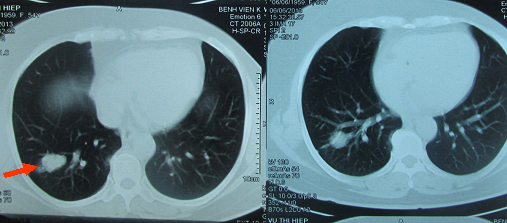

Trên hình ảnh CT lồng ngực: khối u di căn ở phổi nhỏ dần (hình 3).

Hình 3: Hình ảnh CT lồng ngực sau 4 tháng điều trị cho thấy u phổi thu nhỏ nhiều.

Trước điều trị